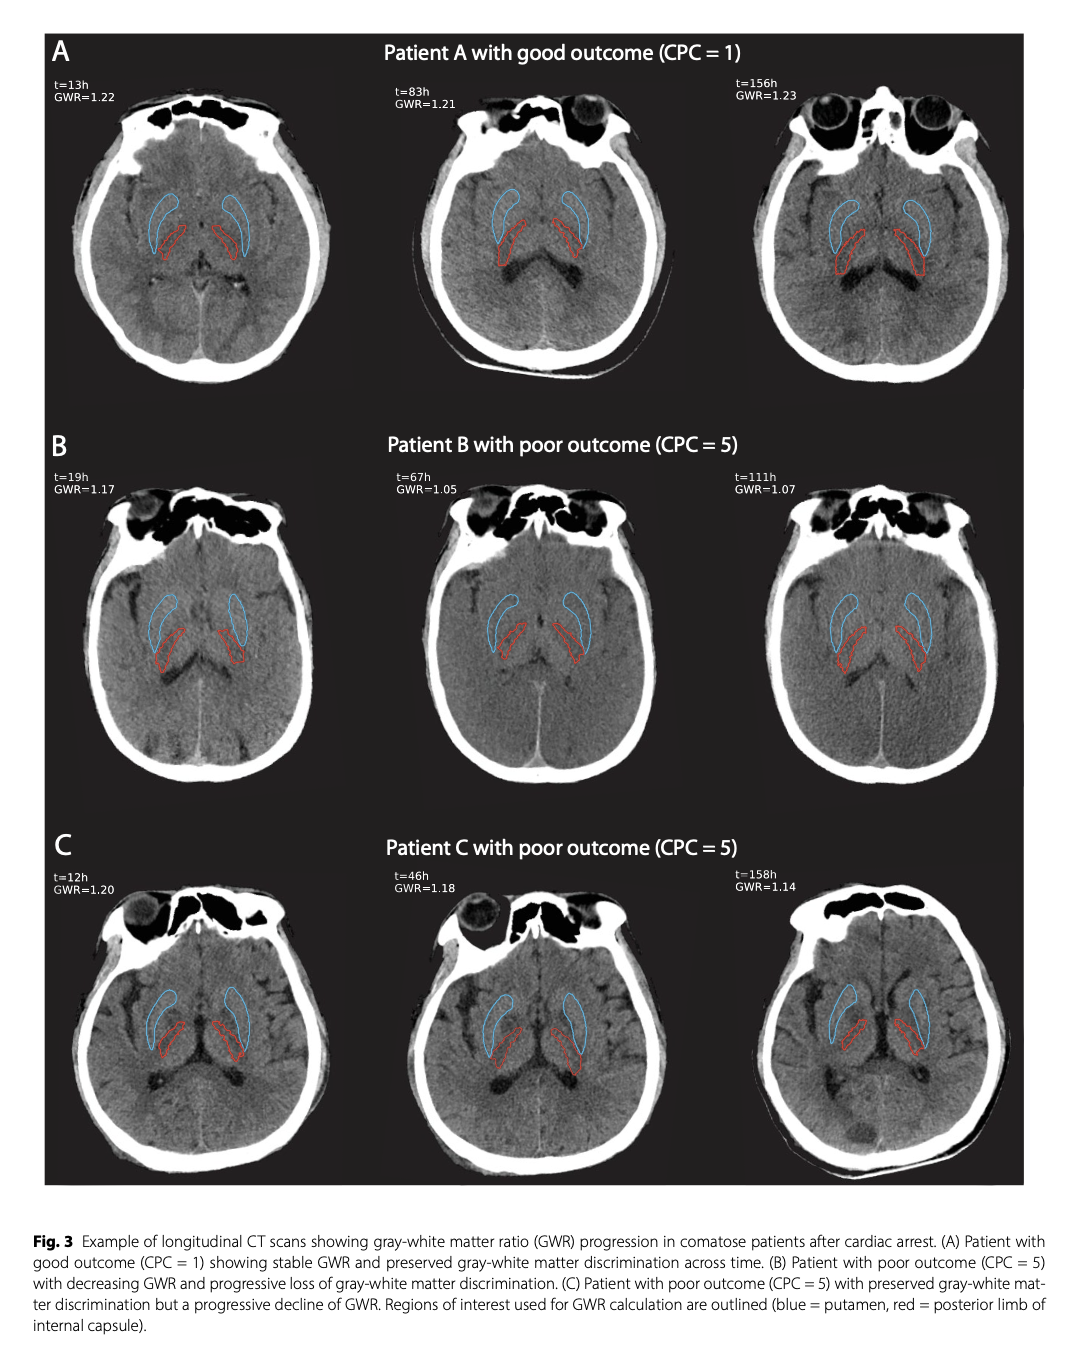

GWR was consistently lower in patients with poor outcomes compared to those with good outcomes across all time windows (for all p < 0.001). In poor-outcome patients, GWR declined after the first 24 h, whereas it was stable in good-outcome patients. The prognostic performance of GWR improved with later imaging, with an AUC of 0.72 (95% CI 0.62–0.81) at < 24 h, 0.78 (95% CI 0.69–0.86) at 24–96 h, and 0.81 (95% CI 0.72–0.88) at 96–168 h after cardiac arrest. Incorporating longitudinal changes in GWR slightly improved prediction, with the AUC increasing from 0.81 to 0.83 at 96–168 h.在所有时间窗口中,预后差的患者GWR始终低于预后好的患者(p < 0.001)。在预后差的患者中,GWR在24小时后下降,而在预后好的患者中则保持稳定。GWR的预后表现随着后期影像学的改善而改善,心脏骤停后< 24小时的AUC为0.72 (95% CI 0.62-0.81), 24 – 96小时的AUC为0.78 (95% CI 0.69-0.86), 96-168小时的AUC为0.81 (95% CI 0.72 – 0.88)。考虑GWR的纵向变化,预测结果略有改善,在96 ~ 168 h时AUC从0.81增加到0.83。

Automated GWR is a useful predictor of outcome after cardiac arrest, with higher accuracy on delayed CT (> 24 h). The different GWR progression trajectories between patients with poor and good outcomes suggest that longitudinal CT assessments may provide additional prognostic information.自动GWR是心脏骤停后预后的有效预测指标,在延迟CT(24小时)上具有更高的准确性。预后差和预后好的患者GWR的不同进展轨迹表明,纵向CT评估可以提供额外的预后信息。